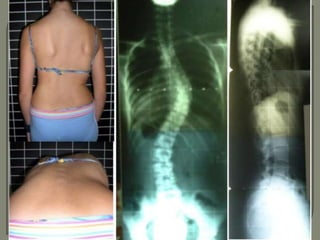

Without intervention, a curve is likely to progress

between the time of detection and the time of

skeletal maturity

The risk of progression

• increases as the degree of

curvature increases

• increases with the magnitude of

the curve at the time of

detection

• decreases with increased age

at the time of detection

Nachemson et al, 1982

Younger girls (ten, eleven, or twelve years old) who had a curve of at least

30o at the time of detection had the highest likelihood of progression,

ranging from 90% to 100%.

Curves that are 20o

or less before the time

of skeletal maturity

are considered mild

and generally are

re-evaluated

every six months.